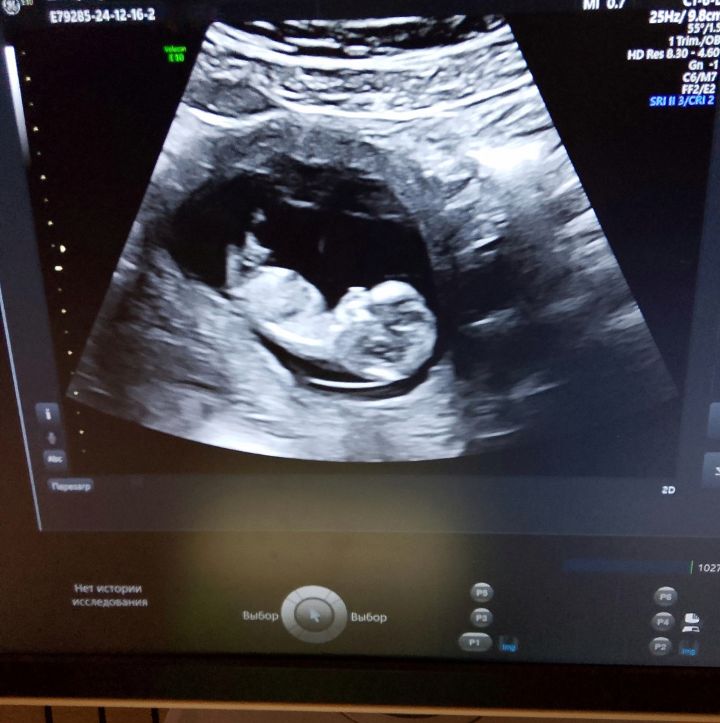

Подскажите, у кого-нибудь определяли пол в 12 недель, хотя бы предположительно, или может кто-то разбирается в этом? Врач на узи сказала, что пол видно будет только с 16 недели. И можно ли что-то понять по снимкам узи? Читала здесь, что у кого-то пол видно было уже в 12-13 недель и не ошиблись)

Обычно видно в 12-13 половой бугорок. Но у вас для этого снимки неудачные, ножкой закрыл малыш.

У вас неудачные снимки. Определить можно с 12 недель ,уже любой нормальный врач может сказать с вероятность 95%

мне с дочкой в 12 недель сказали. по наклону. но у вас не очень хорошо видно

В 12 недель с дочкой определили. Девочки правы, снимки у вас неудачные, бугорка не видно.